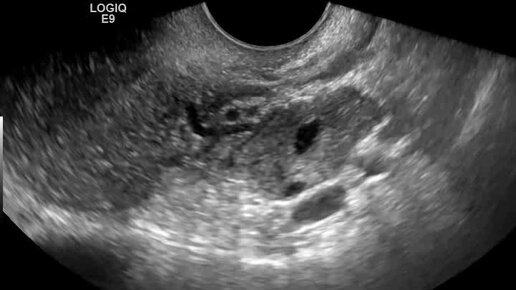

Видео: Поперечное сканирование матки. Левый яичник у угла матки. Спаечный процесс

Ультразвуковые находки от врача УЗД Зорина Я.П.